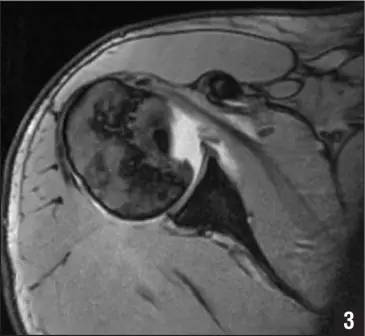

Hill-Sachs 损伤的 MR 片(来源:Hill-Sachs Injuries of the Shoulder)

MRI 示反 Hill-Sachs 损伤程度 (来源:Anatomical Reconstruction of Reverse Hill-Sachs Lesions Using the Underpinning Technique. Orthopedics May 2012 - Volume 35 · Issue 5: e752-e757)